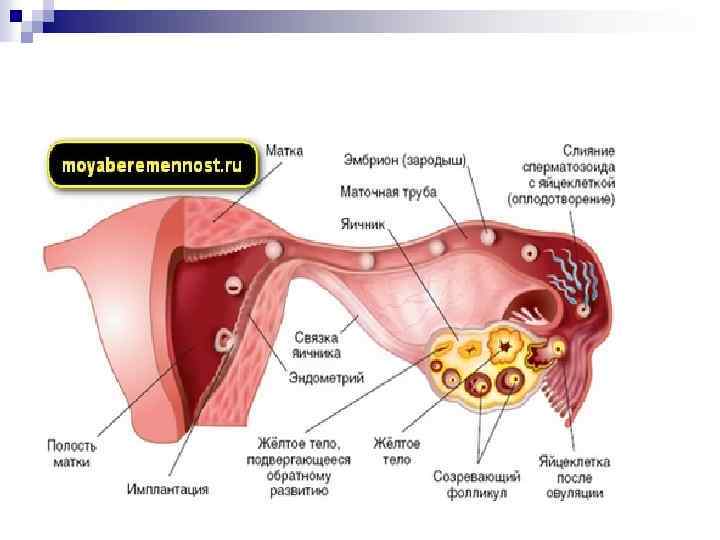

Созревание фолликула в яичнике: этапы и процессы